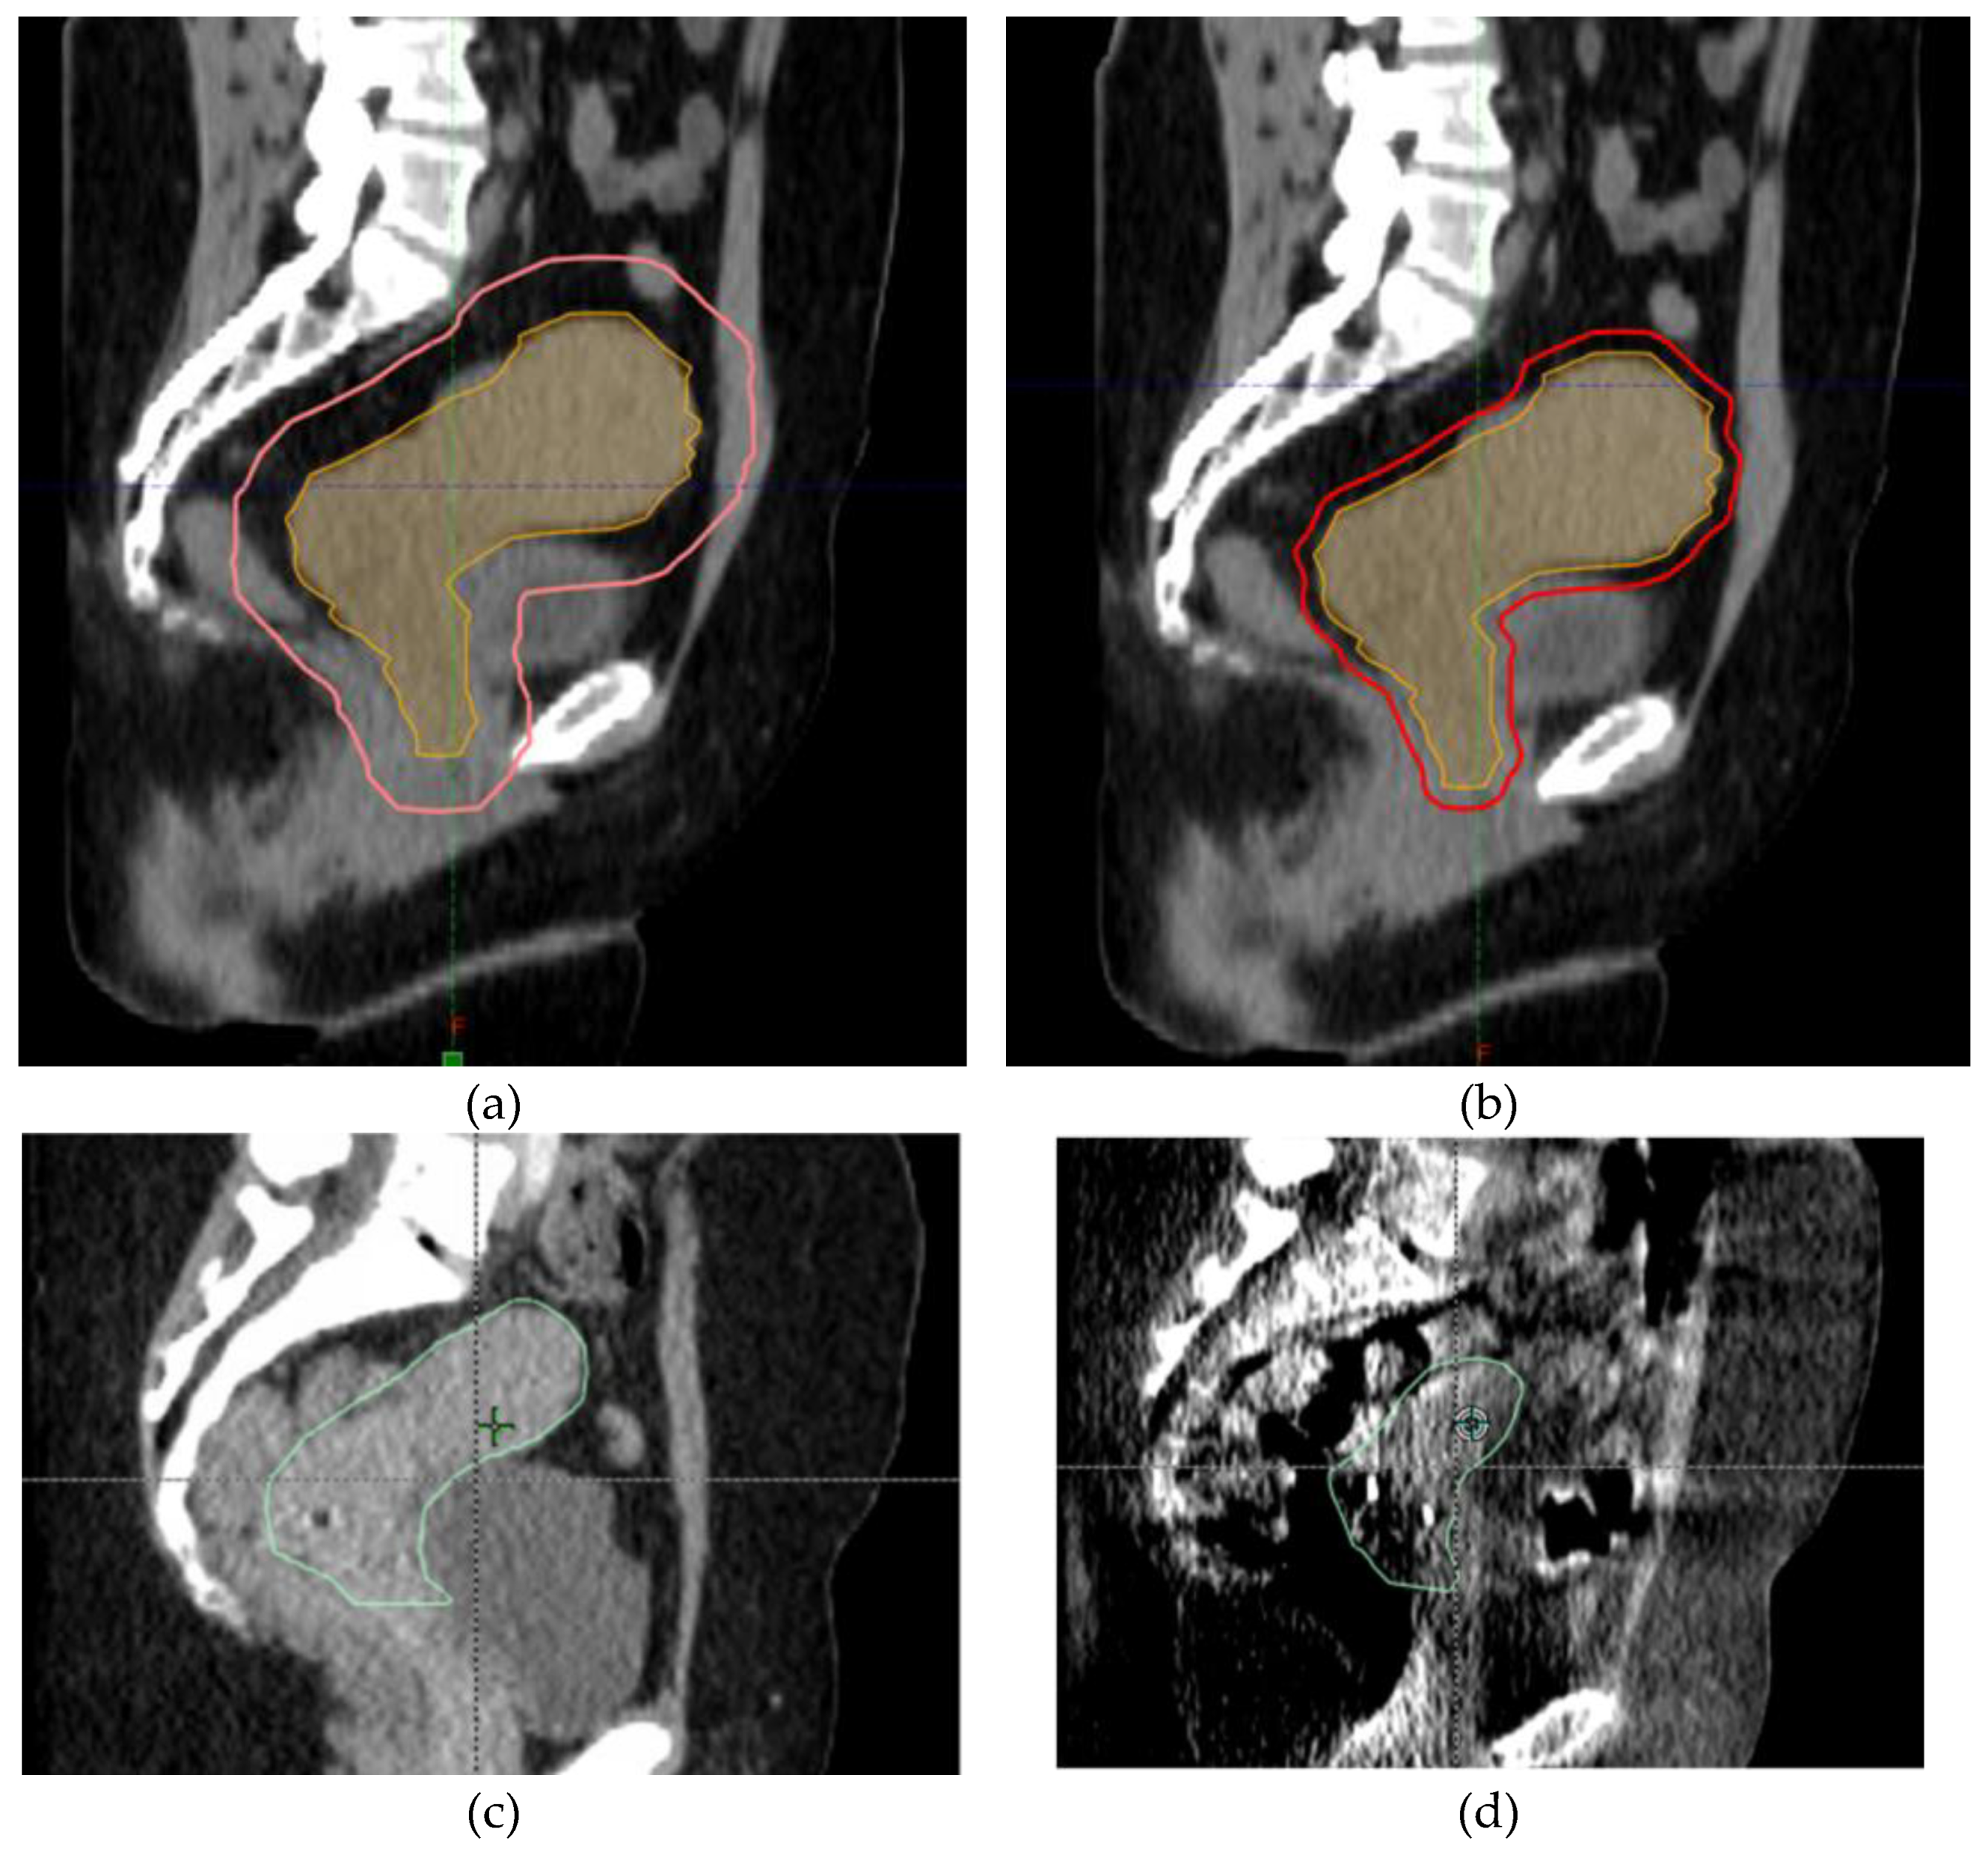

GYN cancers can reap significant benefits from adaptive radiation for two major reasons. First, GYN cancers like cervical cancer can have significant changes in size over the course of treatments. Adaptive radiotherapy is able to account for these changes in tumor size and potentially treat less normal tissue while maintaining tumor coverage. Lastly, the pelvis contains the bladder, rectum, and bowel which can move significantly between treatment fractions. Again, adaptive radiation can account for this interfractional motion and potentially treat less normal tissue. These potential benefits are shown in Figure 3.

Given the large size of her cervical mass, she was determined to be a good candidate for online ART as she was expected to have changes in the size of her tumor, and the reduced CTV to PTV margin could reduce the amount of normal tissue treated. She underwent daily online ART with a 5 mm CTV to PTV margin. She tolerated treatment well except for nausea that was controlled with oral medication. During the course of treatment, her uterocervix decreased in size significantly from 471 cm3 to 191 cm3 as shown in Figure 5. She completed her treatment with brachytherapy with tandem and ovoids. Unfortunately, she later presented with new pulmonary and liver lesions and is undergoing treatment with systemic therapy.

Figure 3. Potential benefits of ART. (a,b) show the decrease in CTV to PTV margins with daily adaptive radiation. The uterocervix CTV is in orange and the PTV is in red; (c,d) show the decrease in target size between the first fraction and last fraction. The uterocervix CTV is in green.

Figure 5. Change in size of uterocervix between fraction 1 and fraction 27 of our patient’s radiation treatment course. The uterocervix CTV is in green.